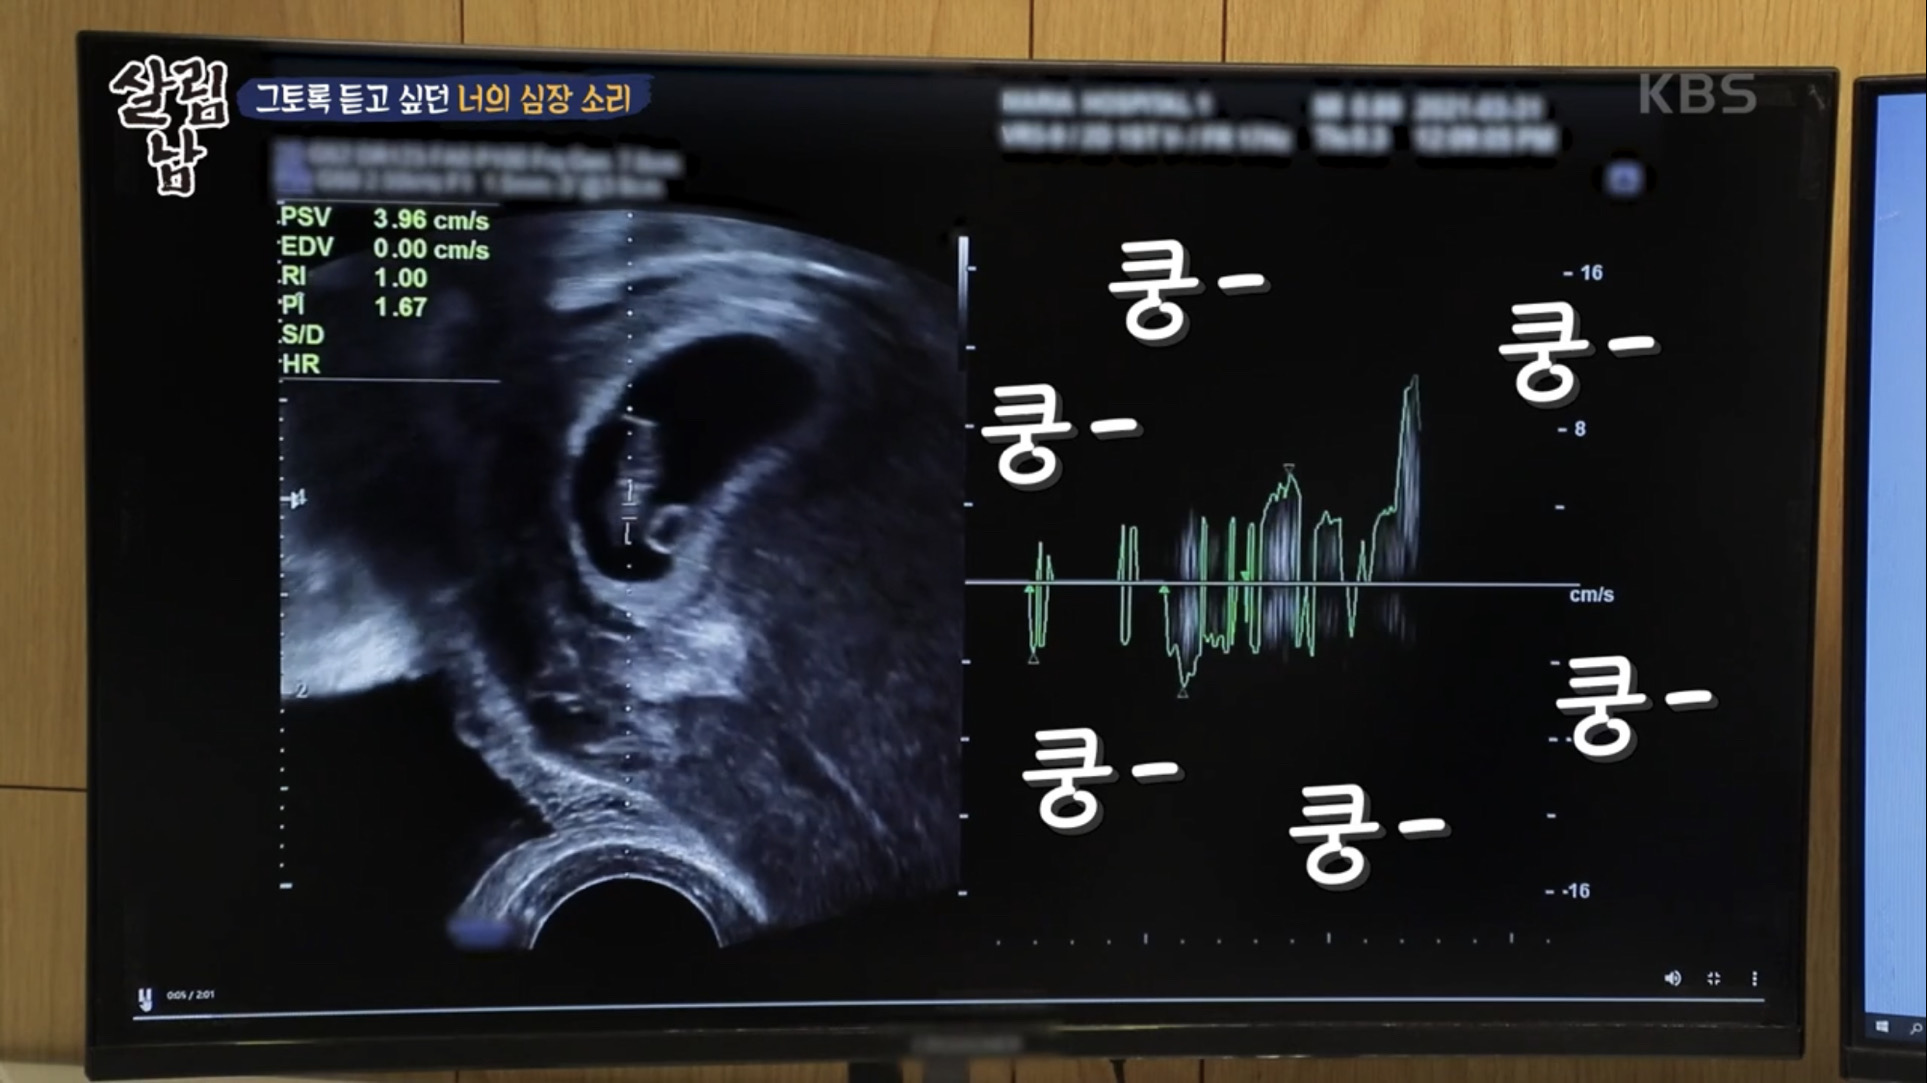

살림하는 남자들 시즌2 202회에서는 윤주만, 김예린 부부가 첫 시험관 시술에 성공해 태아의 심장소리를 들으며 감격하는 장면이 방송되었습니다.

윤주만과 김예린은 병원을 찾았고 의사는 시험관 성공률이 35%에서 40%로 높지 않은 편이고 김예린의 성공률은 20%밖에 되지않았는데 한 번만에 잘 됐다라며 태아의 심장소리를 들려 주었습니다.

윤주만은 이제부턴 좋아해도 되는 건가라고 물었고 의사는 아직 안심할 시기는 아니다조심해야 할 시기다. 10주 정도 되면 안심하는 게 좋을 것 같다라고 조언해 주었습니다.